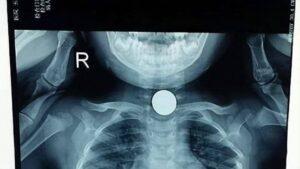

ทั้งคู่รีบพาลูกสาวไปโรงพยาบาลอย่างรวดเร็ว แพทย์และพยาบาลหลายคนพยายามช่วยชีวิตอย่างถึงที่สุด แต่สุดท้ายพวกเขาก็ได้ข้อสรุปว่า “สายเกินไป” ปาฏิหาริย์ไม่เกิดขึ้น หัวใจของเด็กน้อยหยุดเต้นแล้ว หลังจากนั้นแพทย์ทำการตรวจอย่างละเอียด พบว่ามี “ลูกอม” ทรงกลมและแข็งติดอยู่ในทางเดินหายใจ ทำให้เด็กหายใจไม่ออก และนี่คือสาเหตุของโศกนาฏกรรมครั้งนี้